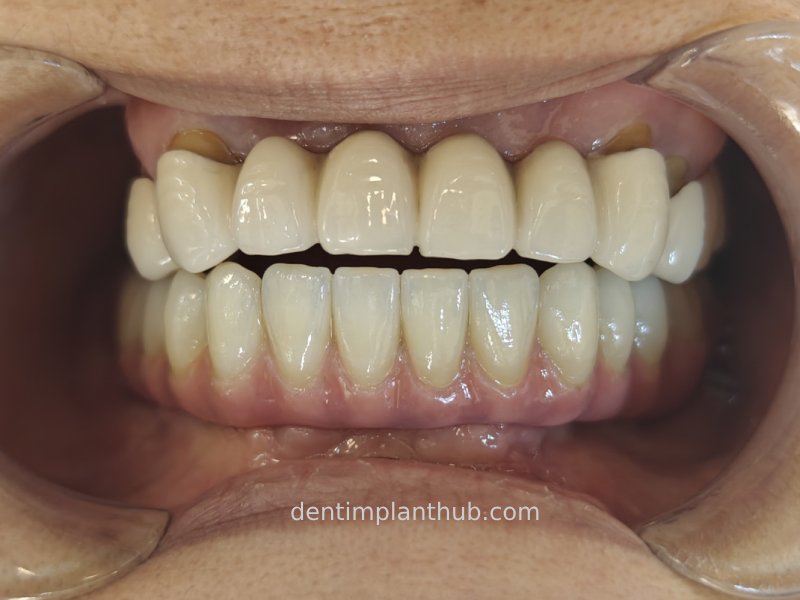

Photo of temporary crown worn into the mouth on the day of surgery, 7 June '24

A fixed prosthesis supported by a Marrowbridge will be worn in the coming months, and the case will be completed at that time.